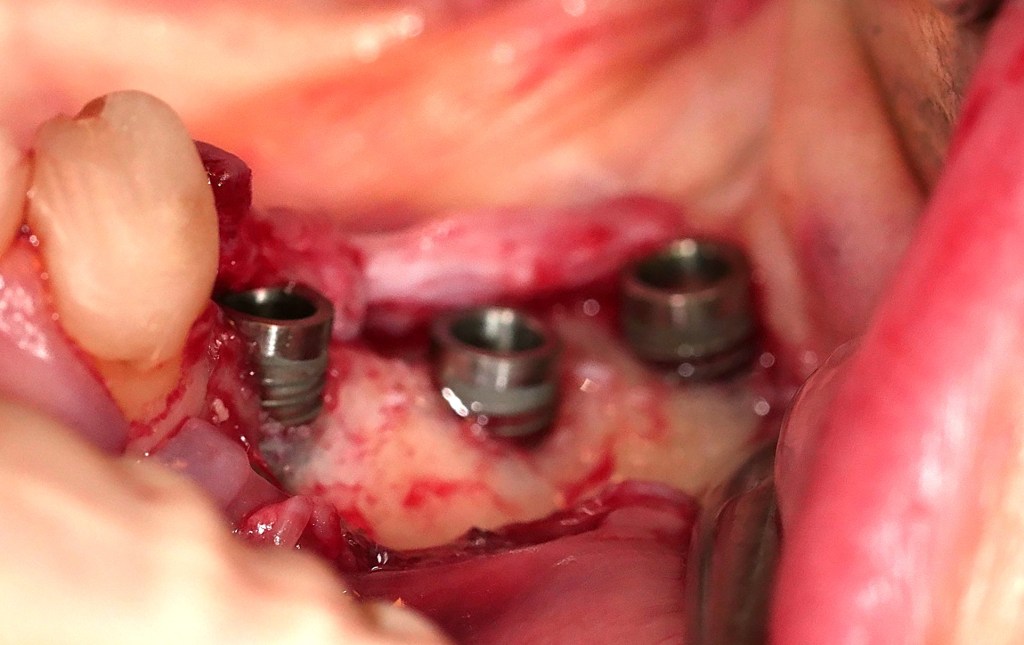

Clinical relevance is further reinforced by Božić et al. (2021), who reported significant improvements in CAL gain and PPD reduction when cross-linked HA was applied in combination with porcine bone graft in intrabony defects. These results support the hypothesis that HA not only serves as a scaffold but also modulates local wound healing biology by favoring fibroblast and osteogenic cell recruitment.

Hard and soft tissue augmentation by fibroblastic stimulation

Taken together, this body of evidence positions cross-linked hyaluronic acid as a promising and versatile bioactive tool in oral regenerative procedures. Unlike other more complex or expensive biological agents, HA provides a straightforward and reproducible clinical approach. It supports soft and hard tissue healing, modulates inflammation, and now, as shown, actively promotes cementoblastic and fibroblastic functions essential for successful periodontal and peri-implant regeneration.